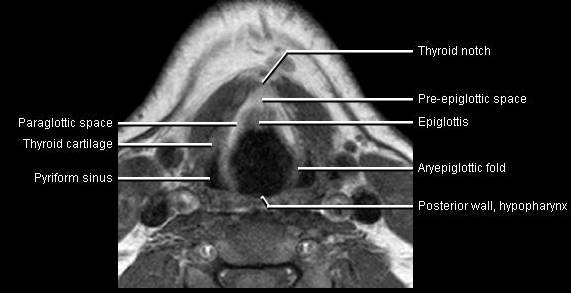

Phonation and dysphagia involve multiple coordinated structures in the larynx and pharynx. Radiation induced dysphagis appears to be related to dose to the phyaryngeal constrictor muscles and specific regions of the supraglottic and glottin larynyx.

Speech is impacted by doses to the epiglottis, base of tongue, aryepiglottic folds, false vocal cords upper esophageal sphincter and cricoid cartilage.

AnatomyCTMR

The mean laryngeal volume receiving > 50 Gy was a predictor of laryngeal edema. Vocal functions are usually well preserved with doses of 60 - 66 Gy. Dornfeld found a strong correlation between speech quality and dose to the ariepiglottic folds, pre-epiglottic space, false vocal cords and lateral pharyngeal walls at the level of the false vocal cords. A steep decrease in dose function was noted when doses exceeded 66 Gy.